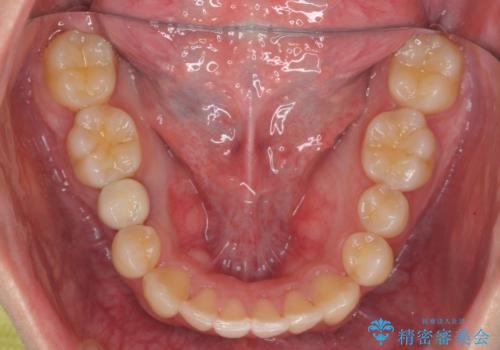

すきっ歯・出っ歯が気になる インビザライン矯正 乳歯をインプラントに

右下に乳歯が残っていましたが、後に続く永久歯がありませんでした。

乳歯も根が吸収しており長くは持たない状況でしたので、まず乳歯を抜歯し、他の歯を矯正治療で歯を並べてからインプラントで補綴しました。

先にインプラントをしてしまうと、矯正治療で周りの歯を動かす事ができなくなってしまいます。

矯正治療→インプラントの順で行います。